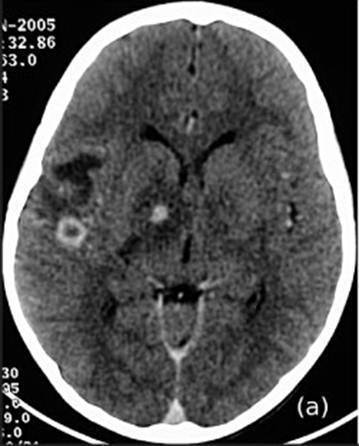

Característica da Criptococose Disseminada 90% dos casos; geralmente afeta SNC

Sintomas da critococose SNC meningite, meningoencefalite, epilepsia

Fase crônica da criptococose do SNC cefaleia, rigidez de nuca, febre baixa ou ausente, visão dupla

Criptococoma cerebral "tumor" de células fúngicas

Espécie relacionada ao criptococoma C.gatti